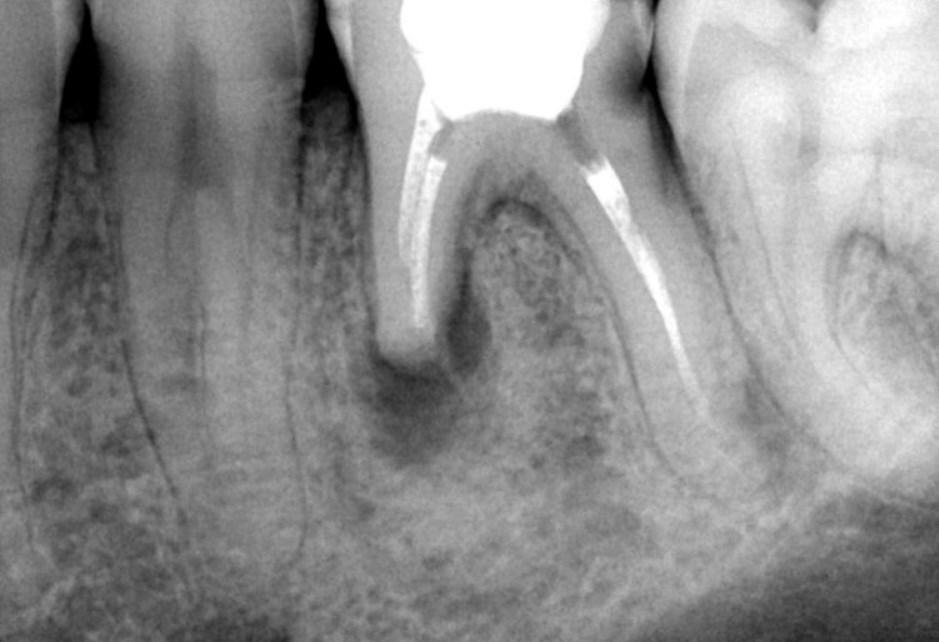

Резорбция может долго не давать о себе знать. У пациента нет боли, отека или дискомфорта, особенно если процесс идет медленно и ограничен небольшой зоной. Это делает регулярные рентгенологические обследования крайне важными — без них патологию можно не заметить до поздней стадии💥

На снимке можно обнаружить:

⚡️Округлые или неровные зоны потери ткани в корне

⚡️Размытые контуры корня

⚡️Изменение длины или толщины корня

⚡️В случае внутренней резорбции — увеличение полости канала